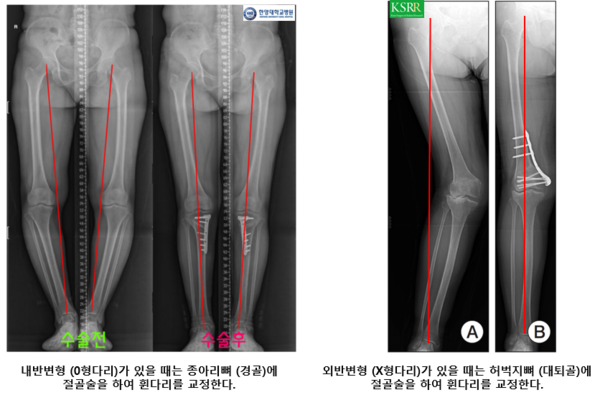

다리를 재정렬시키기 위한 절골술은 하지의 정렬 상태가 정상에 비해 비정상적으로 틀어져있을 때 시행합니다. 그림에서 보시는 것처럼 하지가 정상 정렬일 때는 체중이 전달되는 선(빨간선)이 무릎의 정중앙으로 내려갑니다. 이렇게 되면 내측과 외측에 비교적 균일하게 잘 배분되는데 내반 또는 외반 정렬일 때는 체중이 내측 또는 외측에 집중됩니다. 만약 집중되면 쪽에 병변이 있게 된다면 (예: 내반정렬일 때 내측 무릎 관절의 관절염) 악화될 가능성이 높아서 정상정렬을 만들기 위한 절골술을 고려합니다. 다만 일반적으로 반월 연골판의 파열만으로는 고려하지 않으나 말씀드린 것처럼 관절염의 진행이 관찰될 때 고려합니다.

엠비드의 경우 골반쪽 뼈라고 기사에 나왔는데 아마도 허벅지뼈(대퇴골)을 이야기하는 것 같았습니다. 일반적으로 내반변형 일때는 종아리뼈(경골)에 절골술을 시행하여 교정하고, 외반변형일때는 허벅지뼈에 절골술을 하는 것이 일반적입니다.